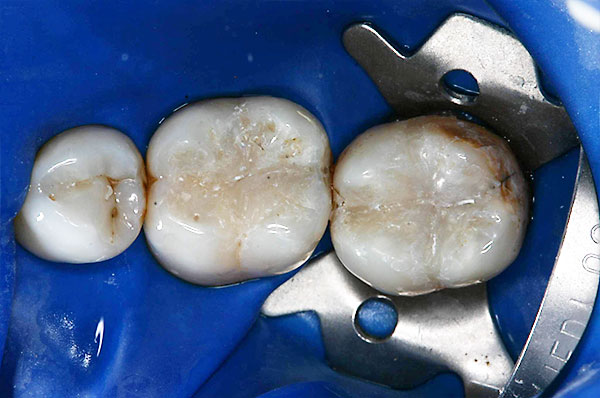

Compositerestauration

![]() |

Zahnärztliche Kunststofffüllmaterialien eignen sich hervorragend für die substanzschonende Versorgung kleiner bis mittelgroßer Defekte am Zahn. Hinsichtlich Härte, Abriebfestigkeit und Stabilität gegenüber Flüssigkeiten (z.B. Speichel) haben sie bessere mechanische Eigenschaften wie Amalgamfüllungen. Bei ausgedehnten Defekten jedoch stoßen die Kunststofffüllungen an die Grenzen ihrer Dichtigkeit und Stabilität. In solchen Fällen ist, je nach Größe der Defekte, Einlagefüllungen wie Keramikinlays, Goldinlays oder Kronen bzw. Teilkronen den Vorrang zu geben.